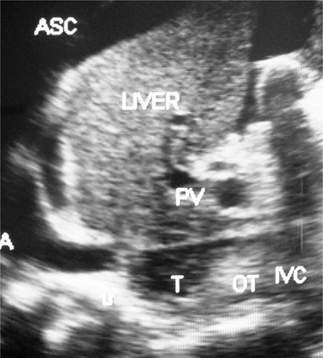

The initial lesion or the thrombus formed during severe AE may extend into HV outlets, resulting in HVOO with sudden development of ascites (Figure 3). Severe AE is likely to develop in persons with poor nutrition or history of alcohol abuse precipitated by puerperal sepsis, chronic bacterial diarrhea, or surgical operation (72, 73). Fever and jaundice usually preceded ascites which is associated with neutrophil leukocytosis, elevated level of C-reactive protein (CRP), and or bacteremia. Ascites in HVCS is invariably associated with bacterial peritonitis (6). About 15% of patients develop pleural effusion (74). US/CD examination (75) and laboratory tests that include total and differential white blood cells (WBC), culture of blood and ascitic fluid, and estimation of CRP are diagnostic of ascites from severe acute/AE of HVCS. This condition responds to treatment with high-dose oral antibiotic for 6–8 weeks, salt restriction, and diuretics.

Fig 3

Figure 3. Hepatic vena cava syndrome: Ultrasonography of a young patient with ascites showing localized stenosis of upper segment of IVC with distal dilated segment of the IVC filled with recent and old organized thrombi. ASC, ascites; IVC, inferior vena cava; OT, organized thrombus; RA, right atrium; T, thrombus. (Copyright: Santosh Man Shrestha).